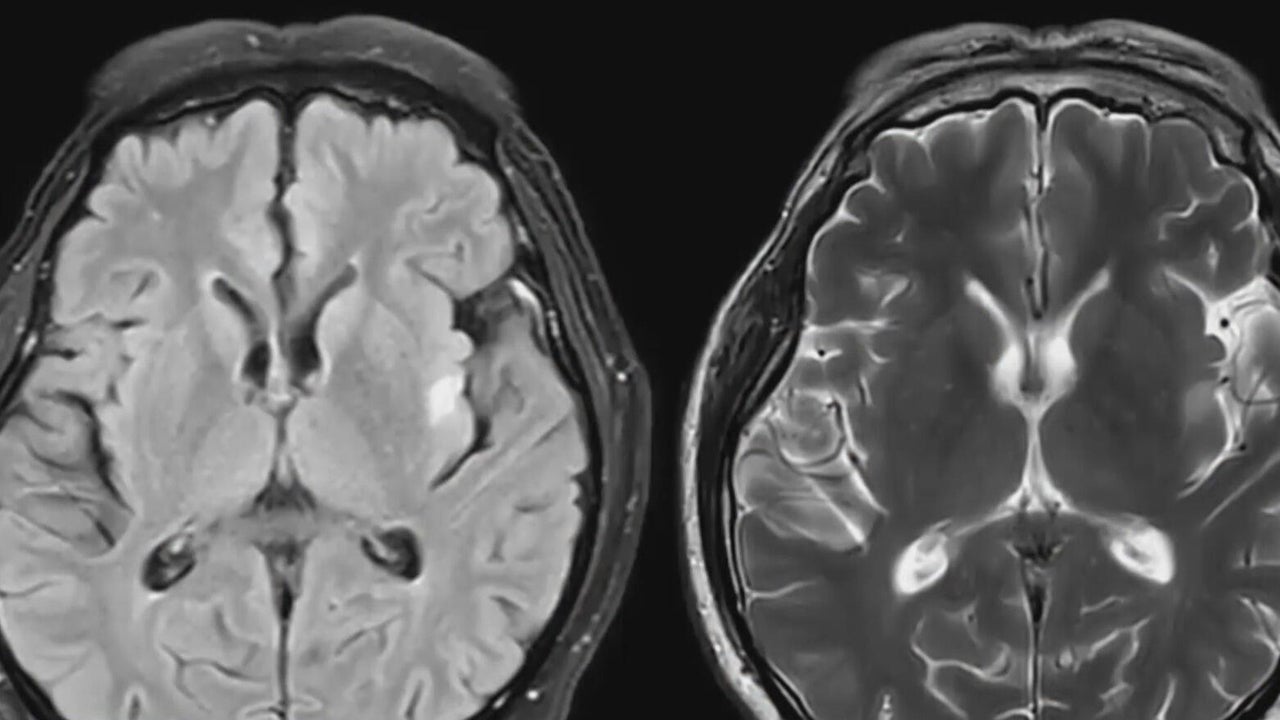

New study on CTE seeks living athletes' data to improve diagnosis, treatment

A groundbreaking new study is underway that could help football players and other athletes who may be more at risk for concussions. Kenny Choi reports.